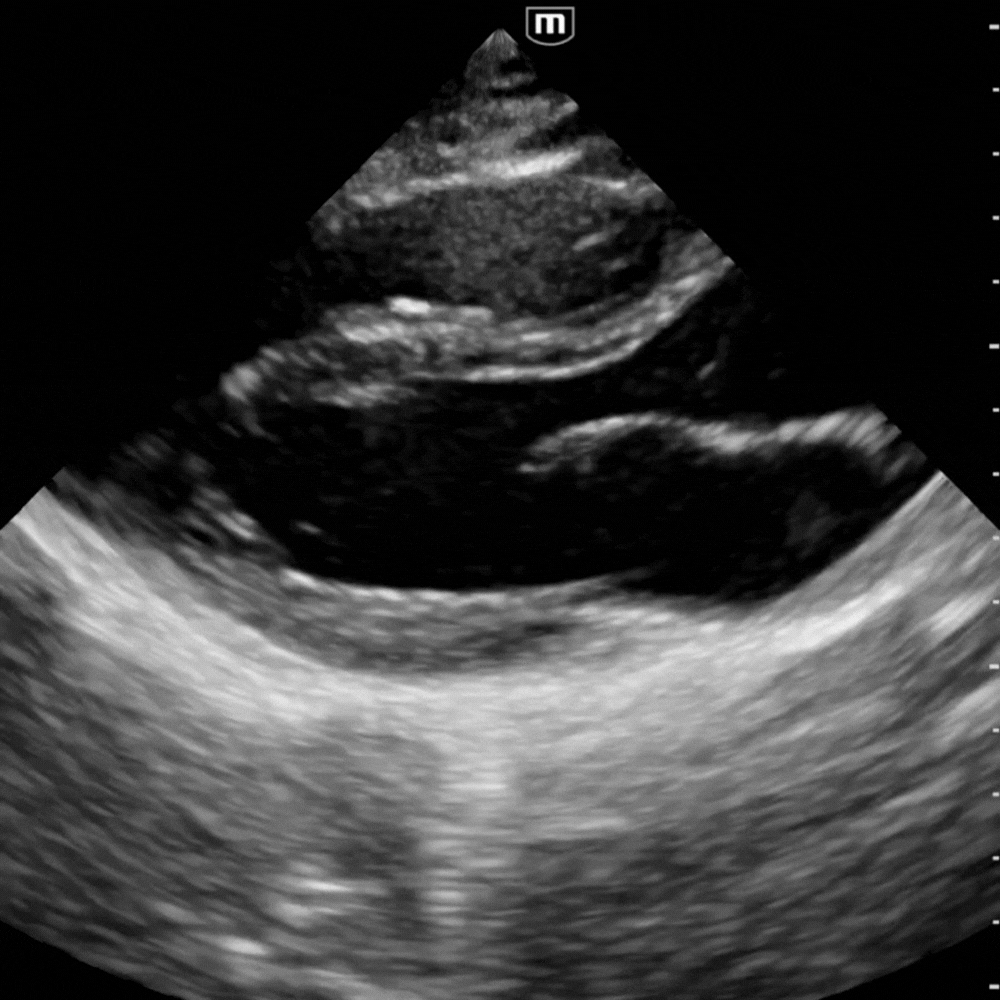

🔹 Vue Parasternale Grand Axe

→ Le cœur se contracte-t-il correctement ?

Sonde au 3ᵉ–4ᵉ espace intercostal gauche, bord sternal, marqueur vers l’épaule droite.

Montre le VG, le VD antérieur, l’oreillette gauche, la valve mitrale, la valve aortique et la racine de l’aorte.

On y évalue :

- la contractilité du VG ;

- la présence d’un épanchement péricardique postérieur ;

- l’aspect de la racine aortique (dilatée, disséquée, hyperéchogène) et la mesure de la chambre de chasse du VG.